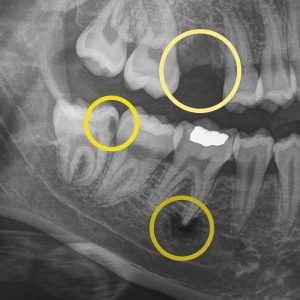

Digital X-rays help your dentist detect concerns early, track changes over time, and personalize your care…